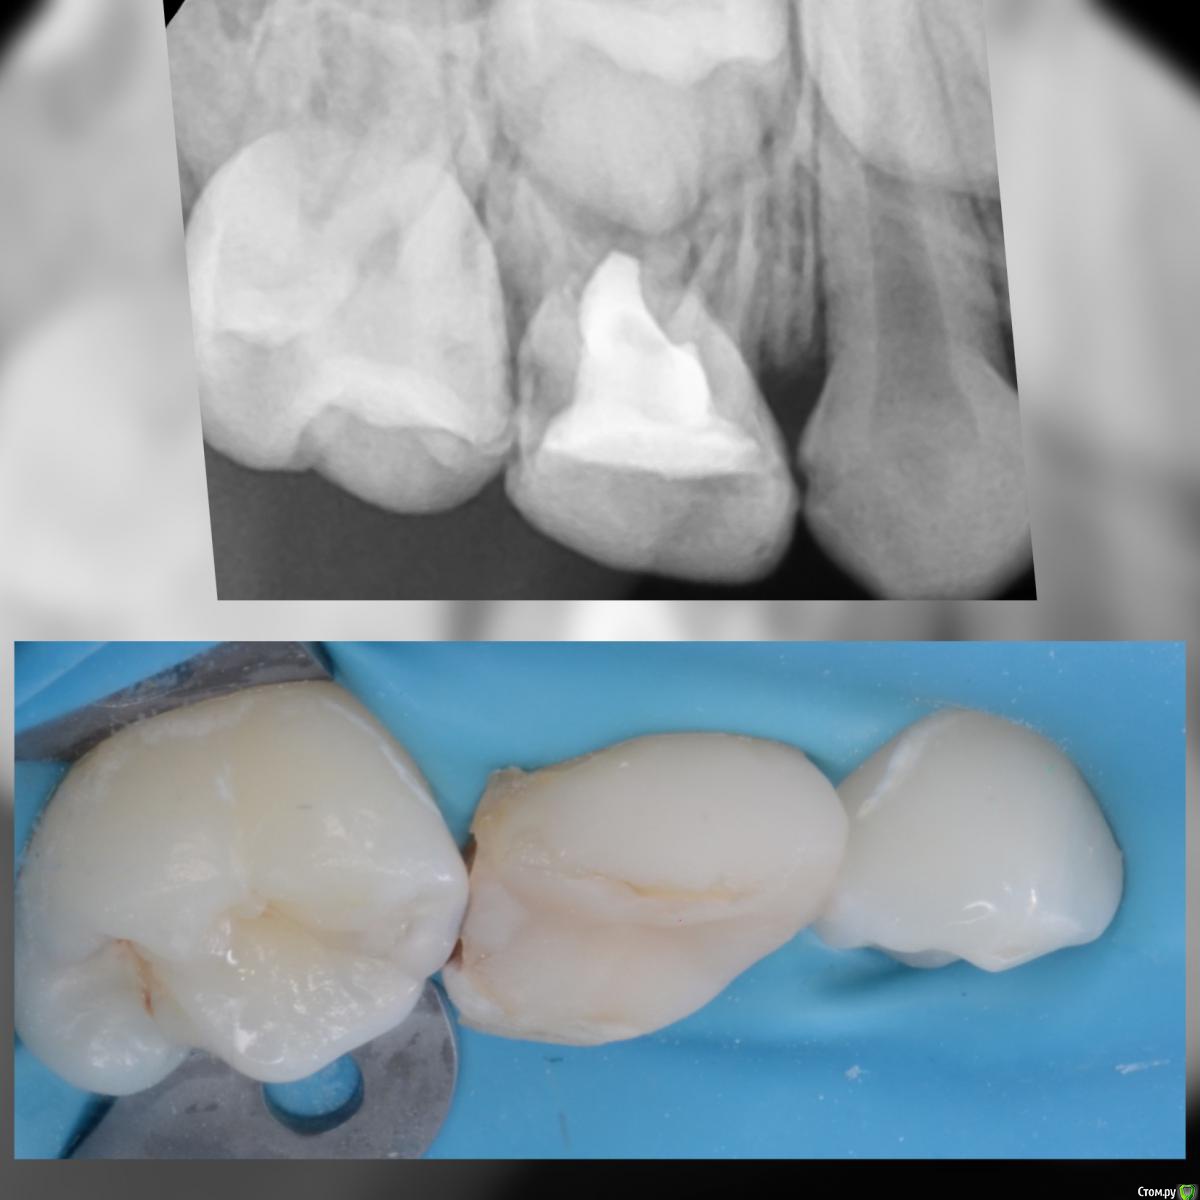

CRAZYDUCK Опубликовано 11 февраля, 2020 Автор Поделиться Опубликовано 11 февраля, 2020 Случай перелечивания через год после лечения в наркозе . Появился кариес на контактных поверхностях . Лечили в ЗакС . Это лечение одного сегмента . Всего пролечила 4 сегмента в ЗакС .девочке 4 годика . На момент последнего лечения очень устала ,на контакт шла с трудом . Но смогли договориться . В наркозе я не лечу , только в ЗакС . В наркоз отправляю к врачам , в навыках и знаниях которых уверена .Лечили кариес клыка и пятого , четвёртый был в наркозе нарощен со всех сторон , поэтому - коронка . 2 Ссылка на комментарий

CRAZYDUCK Опубликовано 20 февраля, 2020 Автор Поделиться Опубликовано 20 февраля, 2020 Верхнее фото - зуб с герметиком . Со слов мамы перед герметизацией зуб не чистили , врач сразу нанёс герметик ( по виду похоже на жидкотекучий композит ).под жидкотекучим был кариес . Убрала жидкотекучий композит рондофлекс , препарирование и восстановление пакуемым и герметиком . 2 Ссылка на комментарий